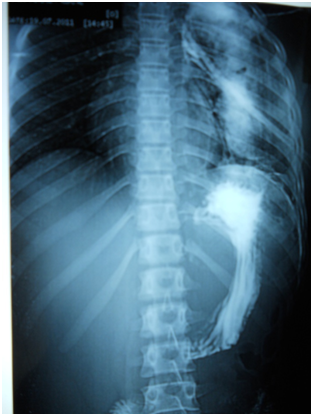

A 17-year-old girl (170cm, 60kg) presented to the emergency department with dyspnea and chest pain after a penetrating stab wound to the chest in the left sixth intercostal space mid-clavicular line, which happened 2hours earlier. Upon physical examination, Pulse was 96 beats per minute and blood pressure was 110/70mmHg, diminished air entry was noticed on the left side of chest. Chest x-ray revealed left hydropneumothorax. Tube thoracostomy was performed left intercostals tube was inserted for drainage. Post-insertion chest x-ray revealed no improvement in the picture of air fluid level (Figure 1) (Figure 2) which was further evaluated by CT that showed fluid collection posteriorly and air anteriorly (Figure 3) (Figure 4). Two days later patient had fever with vomiting and leucocytosis. The nature of the drain from the intercostal tube becomes serosangenous and less hemorrhagic with change in color associated with food. Methylene blue dye (1% concentration) taken orally by the patient was detected in the drain of the intercostal tube two minutes after ingestion (Figure 5). Oral contrast chest x-ray was done, two shots were taken one on swallowing gastrographin, it showed the esophagus outlined without any leakage (Figure 6A). The other shot taken two minutes after oral administration of gastrographin in trendlenberg position, the contrast outlined a track passing from the fundus of the stomach to the left pleural cavity and to the intercostals tube (Figures 6B) (Figure 6C). Laparotomy was performed via midline incision and findings were confirmed. It showed a 3cm orifice of the left copula of the diaphragm with a tear in the gastric fundus which was closed in two layers and the diaphragmatic tear was closed directly with continuous sutures. Two weeks later patient complicated by left empyema with thickened pleura. Thoracotomy was done for complete evacuation of pus and decortication. The patient fully recovered and was discharged 8days after thoracotomy.

Figure 1 Post intercostals tube insertion chest X-ray.

Figure 2 Second day post intercostals tube insertion chest X-ray.